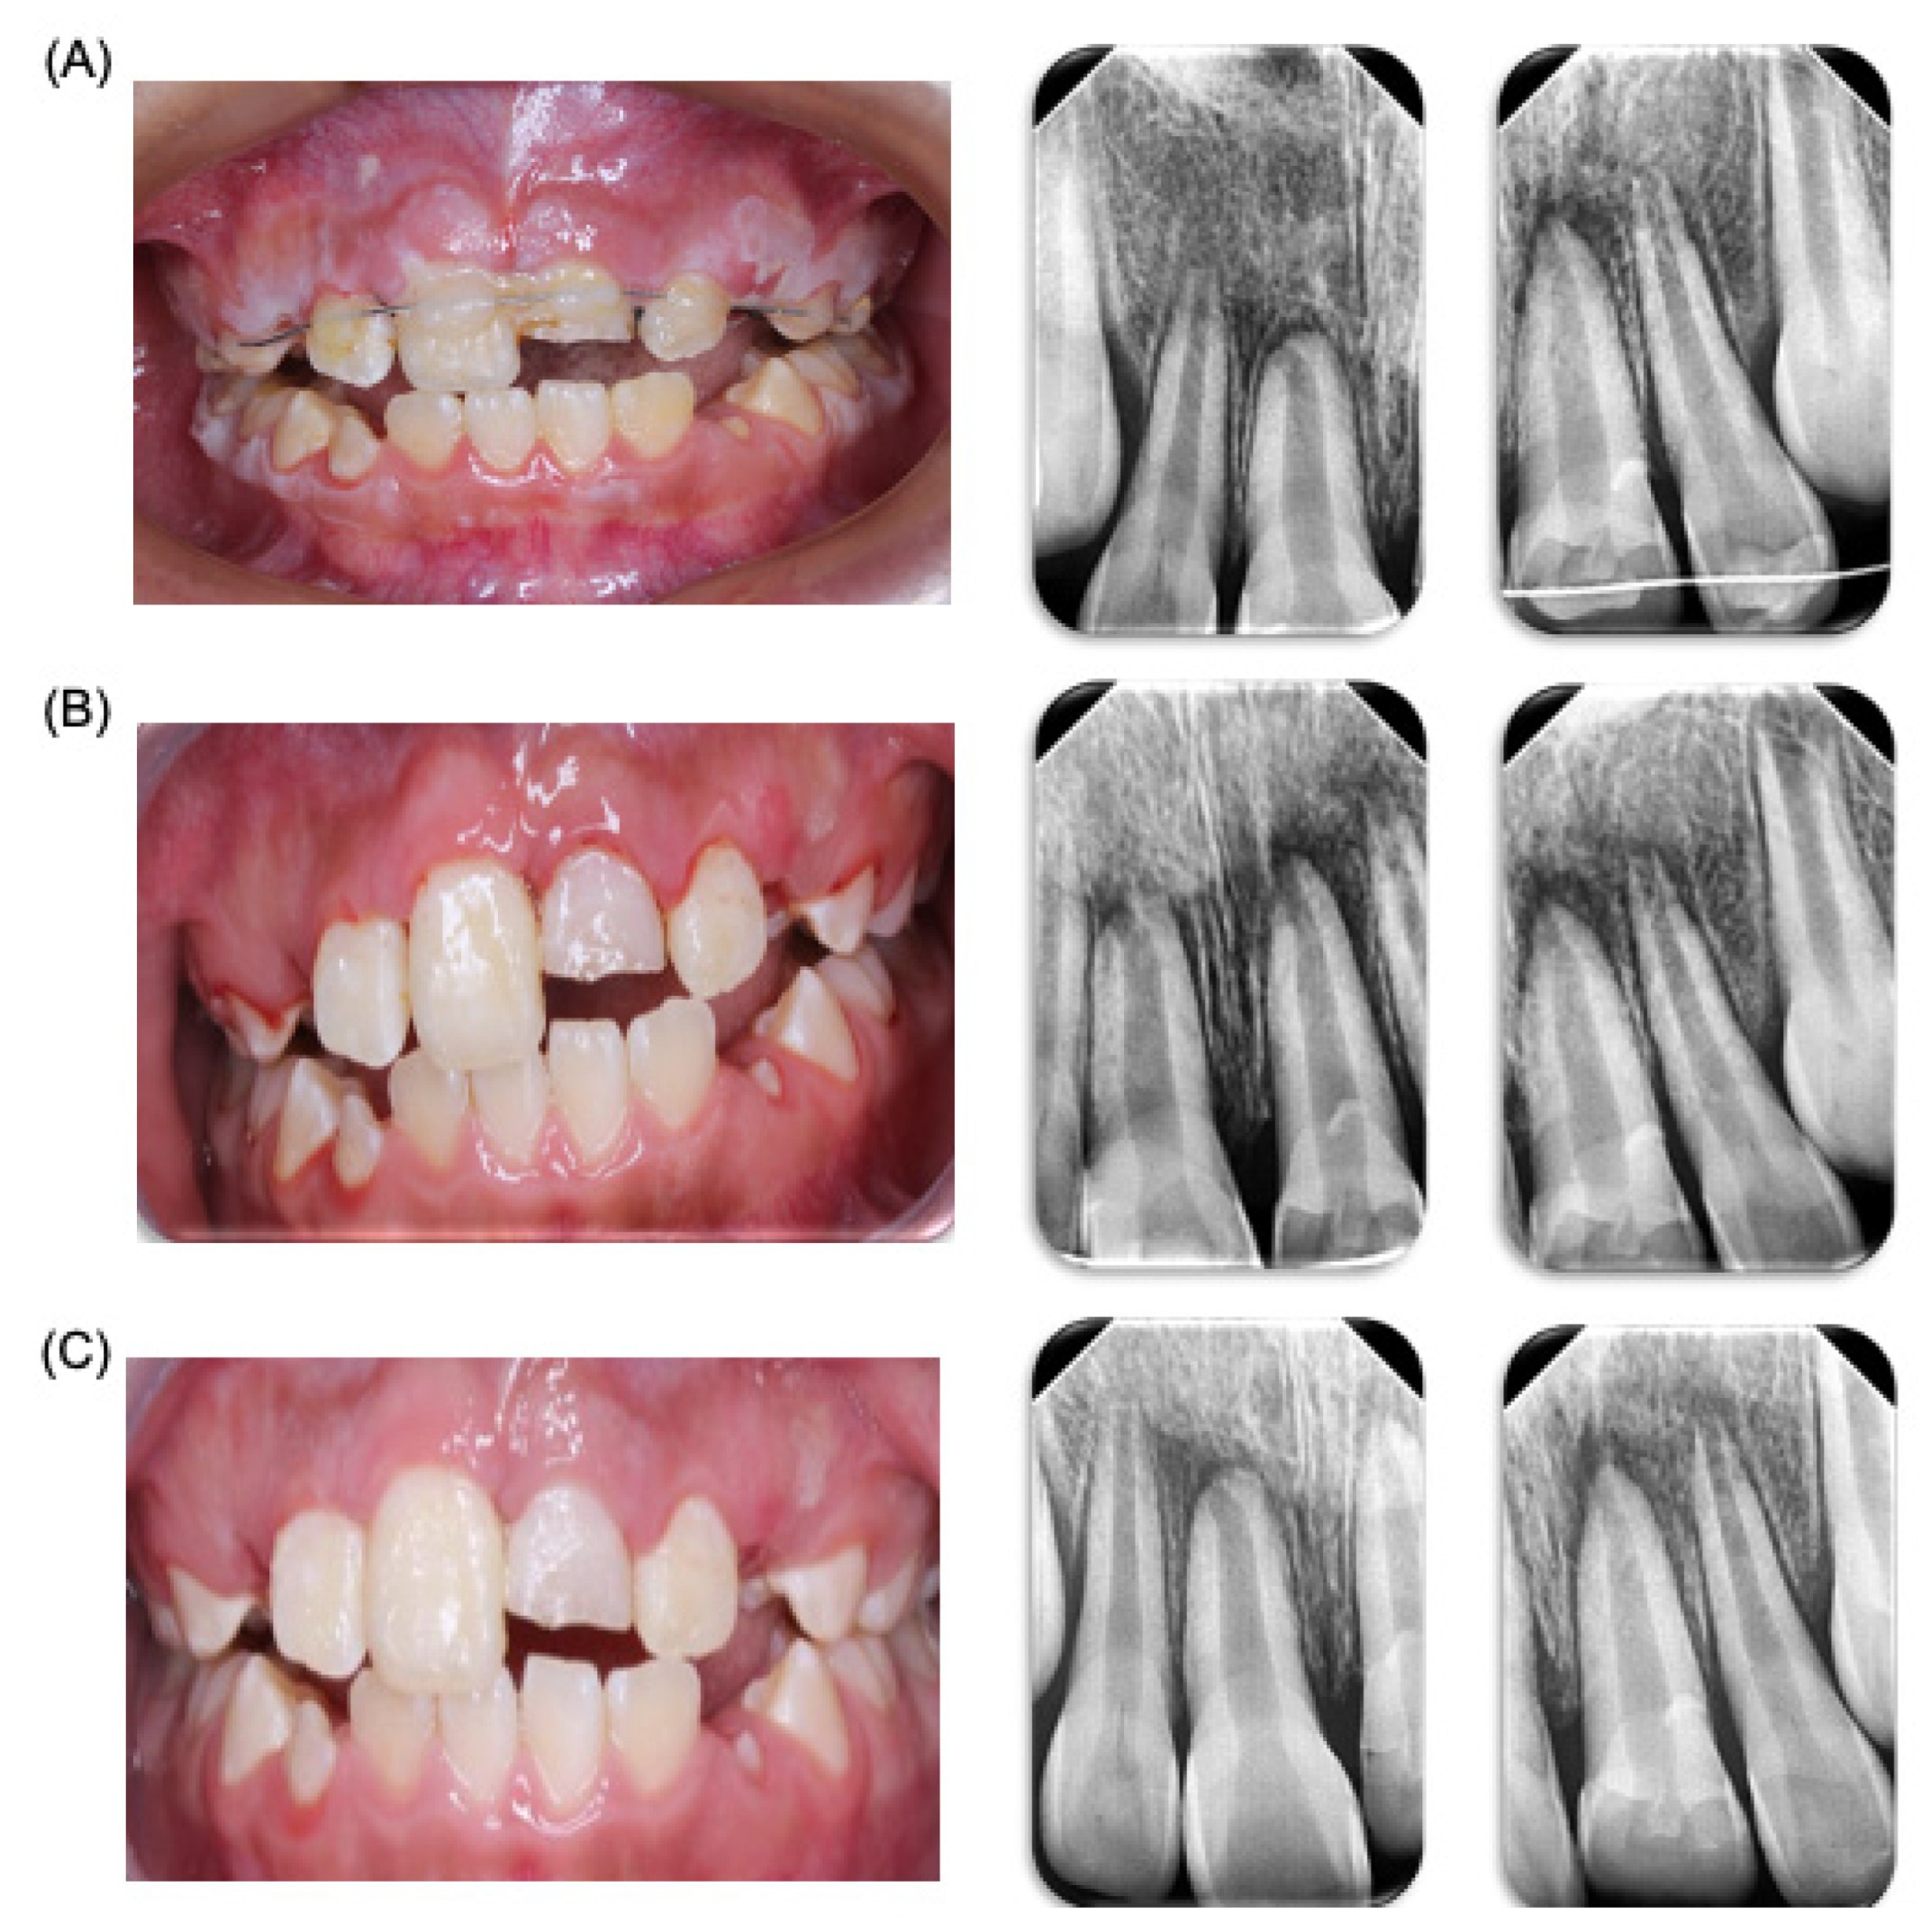

A control appointment was scheduled for one week later, with a follow-up for splint removal in two weeks. In the third week, the patient was referred to an endodontist (Clinic of Endodontics, Endodontics Postgraduate Program, Faculty of Dentistry, Autonomous University of San Luis Potosi, SLP, Mexico) for vitality tests. At the follow-up appointment, the patient was asymptomatic but exhibited poor oral hygiene with generalized dental plaque. Instructions were given for the modified Bass brushing technique with a soft-bristled brush. Sutures were removed, periapical radiographs were taken, and the patient was advised to continue with a soft diet. One week later, the patient returned for another control appointment. He was symptom-free and showed improved hygiene. The brushing technique was reinforced, the splint was removed without complications, and additional periapical radiographs were taken. The patient was then referred to the endodontist for further evaluation (Figure 2). Four days later, the patient returned to the pediatric stomatology clinic, reporting additional trauma from a classmate hitting him on the upper anterior teeth. A panoramic X-ray was taken for evaluation. During the physical examination, no new alterations were observed, so continued observation was recommended (Figure 2).

Figure 2.

Dental trauma follow-up. Control and clinic and radiologic follow-up of patient. (A) Clinic and radiological revision one week after accident. (B) Clinic and radiological revision two weeks after the accident. (C) Clinic and radiological revision due to the new trauma.